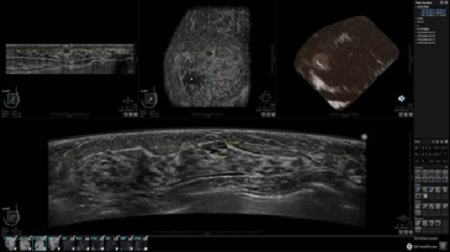

GE INVENIA ABUS – это современный УЗИ аппарат, который создан для точной и эффективной диагностики сканирования с высокой плотностью молочных желез. Выявляемость патологий раковых и предраковых стадий заболевания составляет 55%, что в конечном счете позволяет ставить врачу точные и своевременные диагнозы. Традиционные методы использования маммографии не показывают такой выявляемости, ограничиваясь лишь 3-38%.

УЗИ-аппарат GE INVENIA ABUS позволяет проводить максимально операторонезависимые процедуры, что значительно снижает риск неправильной постановки диагноза и сопутствующие издержки на обработку информации. Система готовит отчет в течение 3-х минут после сканирования, это безусловное преимущество по сравнению с обычным УЗИ сканером.

• Получение объемных 3D изображений с возможностью покадрового просмотра

• Получение изображений в поперечной плоскости (в реальном времени) и в коронарной плоскости (статическая, для указания нахождения соска)

• Отображение объемных 3D ультразвуковых изображений, которые состоят из традиционных поперечных и воссозданных коронарных и сагиттальных проекций

• Возможность отображения полного 3D изображения

• Стандартизованная ориентация изображения: «толстый срез» в коронарной плоскости; поперечная; сагиттальная плоскость; радиальный и антирадиальный поворот изображения; просмотр исключительно области интереса

• 360 ° APC - отображение области по «любой точке компаса»